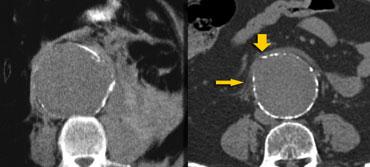

Các dấu hiệu chính của vỡ phình động mạch chủ bụng (AAA) bao gồm: thâm nhiễm mỡ quanh động mạch chủ, tụ máu sau phúc mạc và thoát thuốc cản quang tiêm tĩnh mạch.

TRÁI: Thâm nhiễm mỡ quanh động mạch chủ mức độ nhẹ, GIỮA: Xuất huyết vào khoang cạnh thận sau và quanh thận, PHẢI: Thoát thuốc cản quang tiêm tĩnh mạch

Bên trái là hình ảnh của ba bệnh nhân bị vỡ phình động mạch chủ.

Trong hình ảnh ngoài cùng bên trái, chúng ta chỉ thấy một ít mô mềm tỷ trọng cao ở ngoại vi tiếp giáp với túi phình, và đây thực sự là dấu hiệu cho thấy bệnh nhân có nguy cơ vỡ hoàn toàn.

Hai trường hợp còn lại cho thấy tụ máu sau phúc mạc và thoát thuốc cản quang ra ngoài động mạch chủ, giúp chẩn đoán dễ dàng hơn.